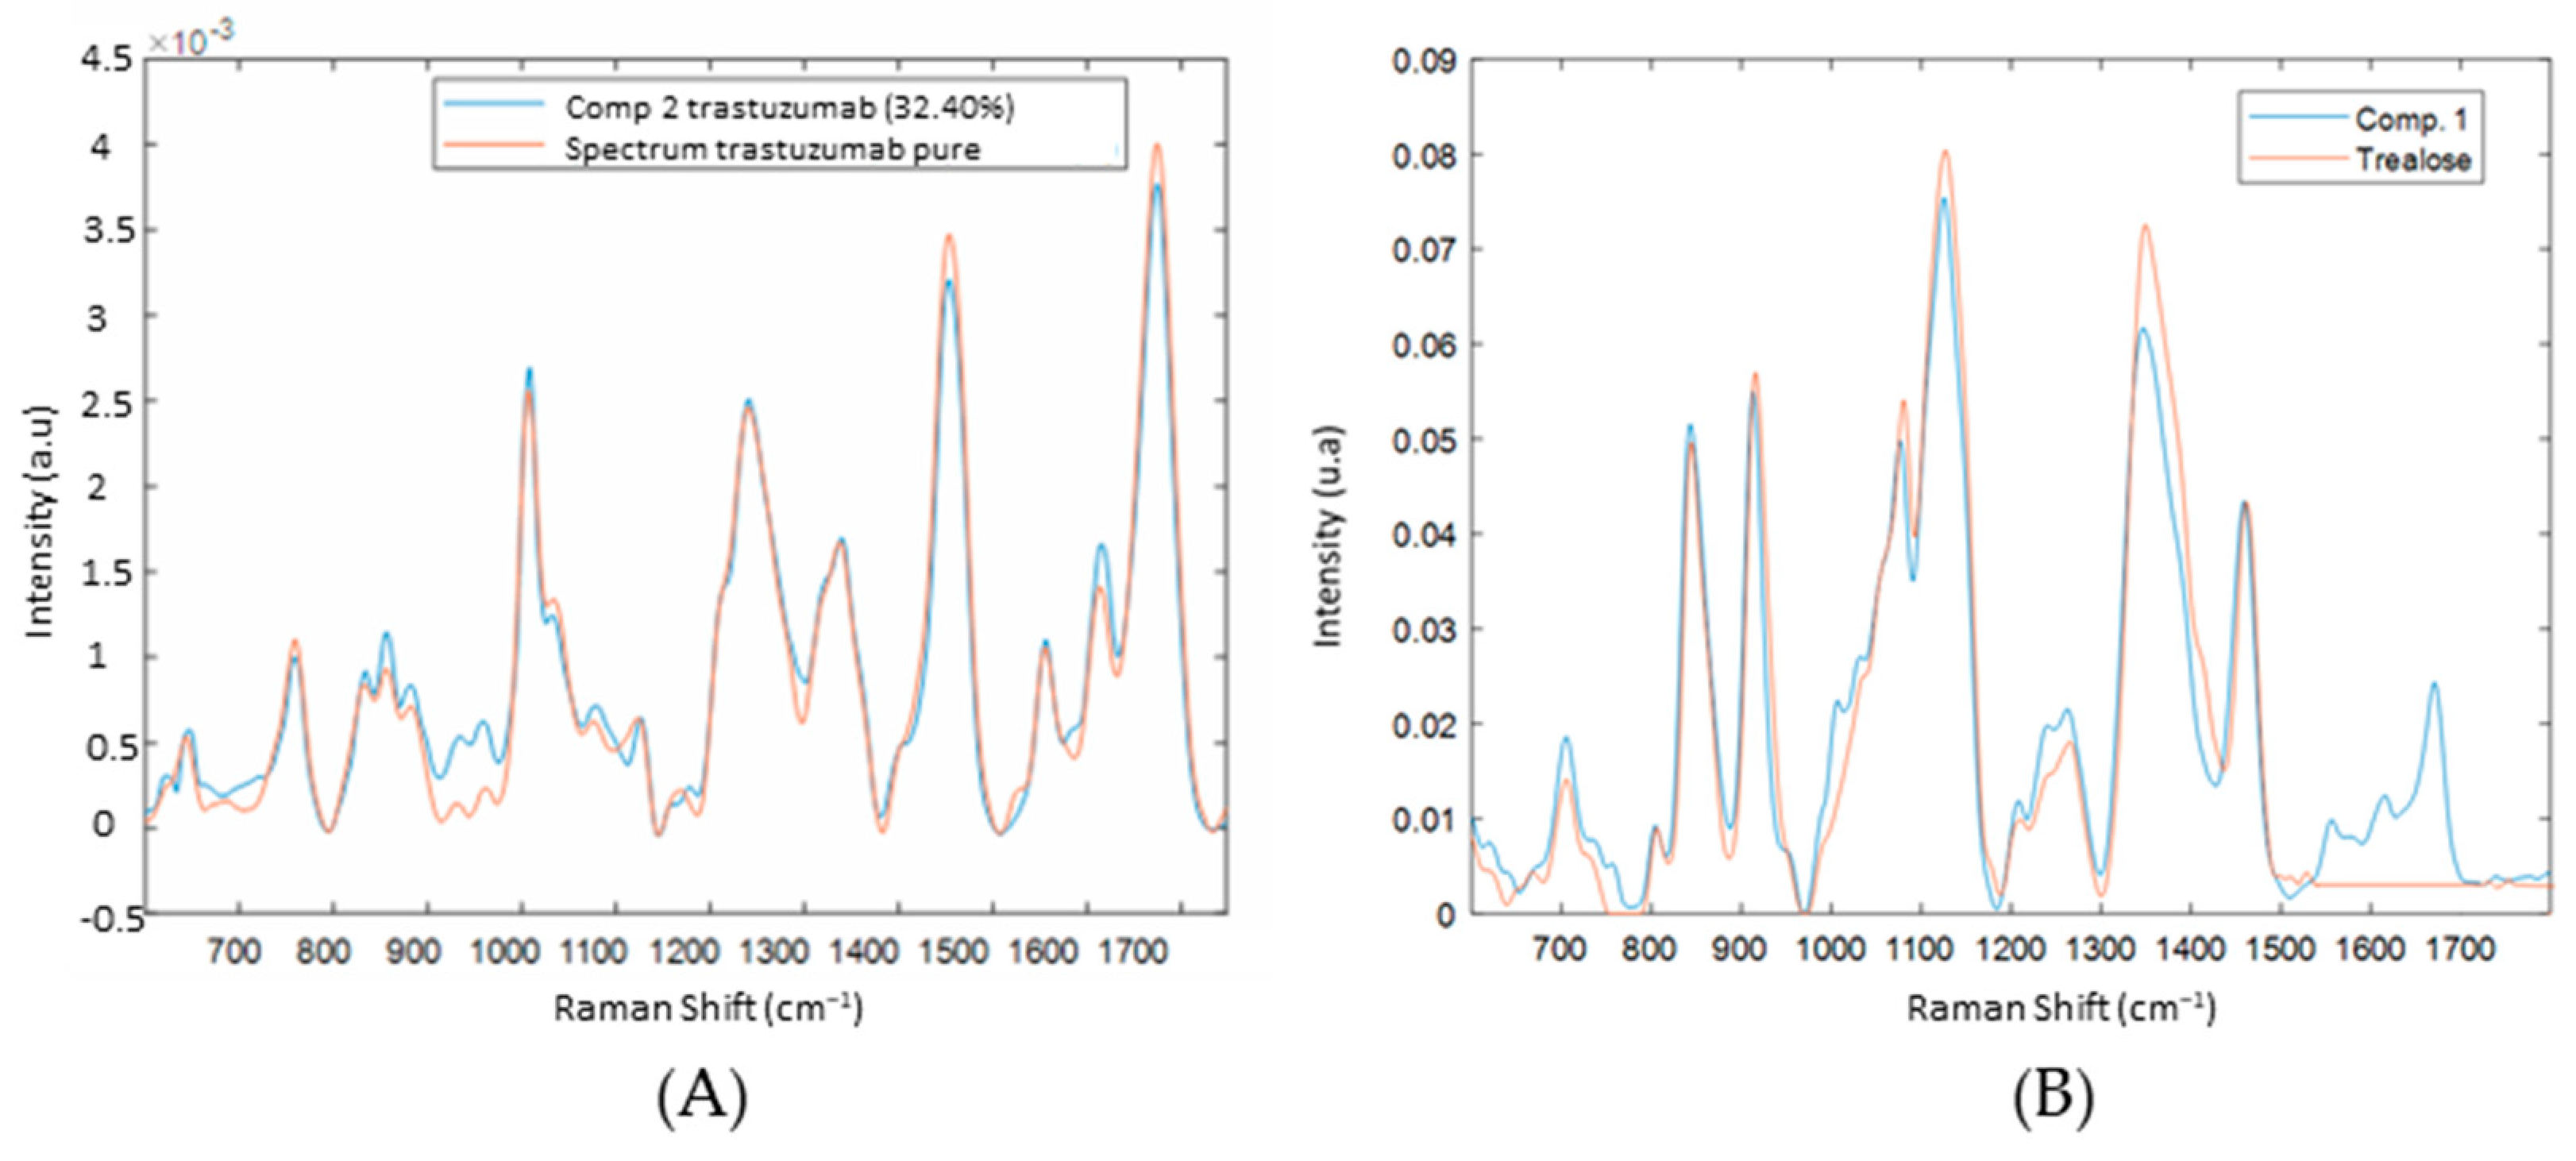

3.2. Spectral Characterization of Commercial mAbs Solutions by DCDR Imaging and MCR-ALS Analysis